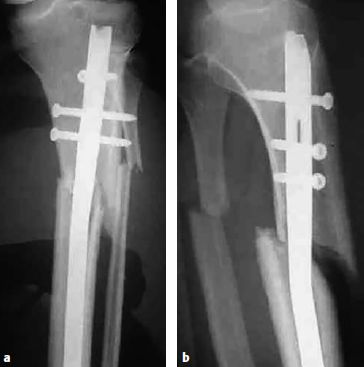

临床应用LISS钢板或者锁定加压钢板于胫骨近端骨折能在骨折愈合、感染率以及二期复位丢失方面得到优秀的结果[12](图6.8.1‑17)。若内侧皮质严重粉碎或者缺损较大,则需要在额外加一块内侧钢板来避免二期力线丢失和内翻畸形[13]。

图6.8.1-17 a-n 一名62岁的男性车祸后左腿受伤(41A3.3)

a-b  X线显示左侧胫骨的节段性骨折。骨折近端有多条骨折线和一个楔形骨块,但是它们都没有移位或移位程度很小。整个骨折可以通过一根髓内钉进行固定,但是由于骨折位置非常高位,因此髓内钉手术将非常具有挑战性,因此最终选择采用MIPO技术进行钢板固定

c-d  关节面的骨折通过软骨下螺钉进行稳定固定,使用点式复位钳通过微创技术经皮复位近端的干骺端骨块,滑入胫骨近端锁定加压钢板,而后使用两枚克氏针在钢板两头进行临时固定